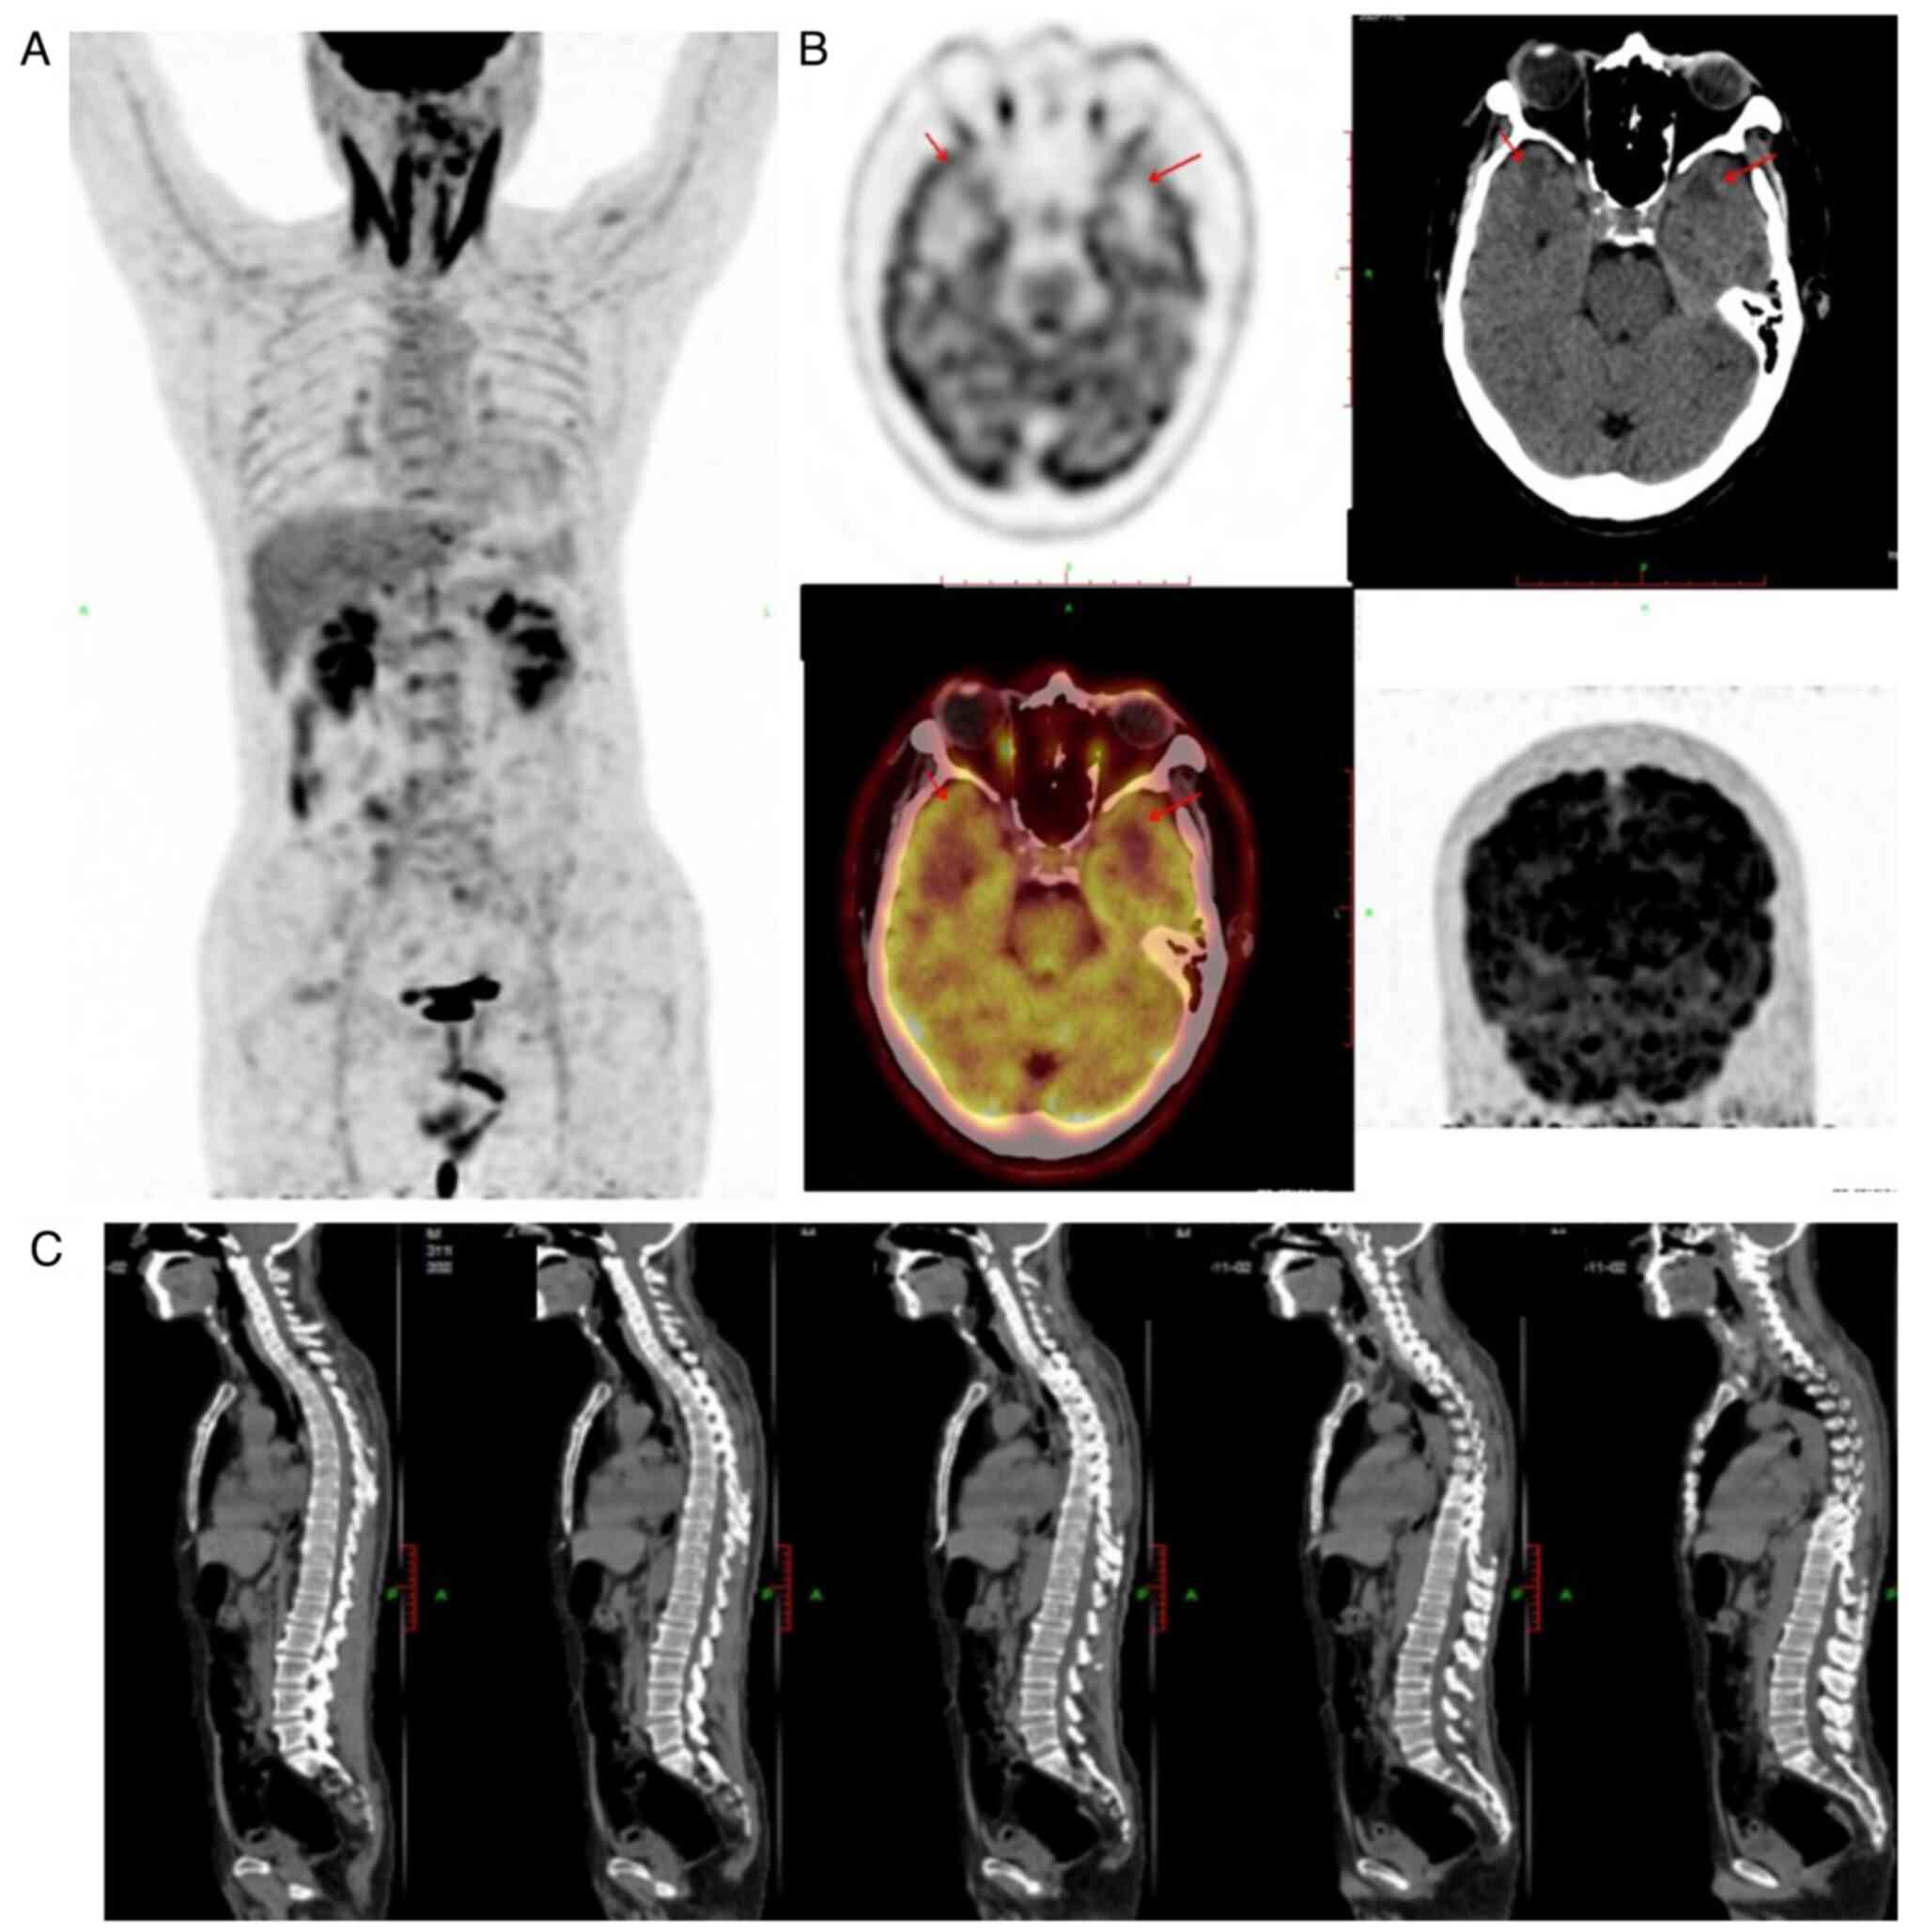

Primary central nervous system (CNS) lymphoma of the meninges is a rare tumor that originates in the meninges and does not show parenchymal or systemic spread. CNS involvement by natural killer (NK)/T‑cell lymphoma accounts for only 2% of all extranodal NK/T‑cell lymphomas, and primary NK/T‑cell lymphoma of the meninges is even rarer. The present study reports a case of a 55‑year‑old male patient with primary NK/T‑cell lymphoma. The patient presented with intermittent dizziness and headaches for the past 1 month prior to presentation. Magnetic resonance imaging of the head identified no overt abnormalities. However, cytological analysis of a Wright‑Giemsa‑stained cerebrospinal fluid (CSF) sample, demonstrated numerous atypical lymphocytes and lymphoma cells. Flow cytometry of the CSF was performed as an auxiliary method, and it showed that a large proportion of the cells in the CSF were of the NK/T‑cell lineage, to indicating a diagnosis of NK/T‑cell lymphoma. Mutations of 14 genes were detected, including JAK3 mutations, upon screening of the CSF for blood system diseases using next‑generation sequencing. Therefore, the present study demonstrated that a CSF cytological examination may be an important component of the diagnostic workup for patients suspected to have a primary meningeal CNS lymphoma.

Figure 1

Figure 2

Figure 3

Figure 4